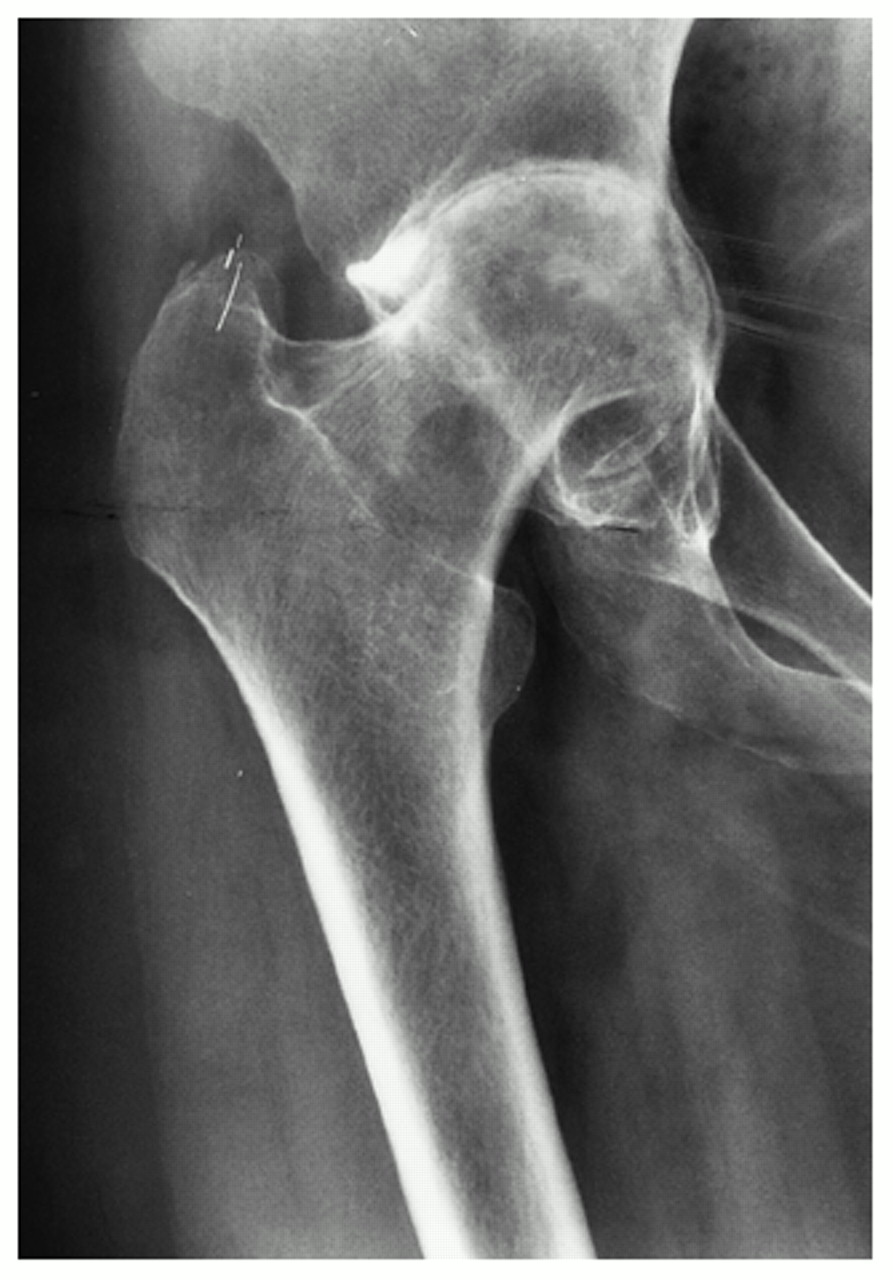

Rheumatic arthritis causes joint erosion and joint destruction visible on x-rays and symptoms that can be severe and limiting. As the joint becomes eroded the cartilage is damaged and the articulation of bone-on-bone causes severe pain. Damage to cartilage, tendons, ligaments and bone causes the hip joint to become deformed and even unstable as rheumatoid arthritis progresses.

The frequency of acetabular protrusio is higher in rheumatoid hips as is the likelihood of significant femoral head deformity. Bone quality is poor especially in those patients who have needed long term steroid treatment. This makes these operations more difficult, with a higher risk of per-operative and post-operative complications.